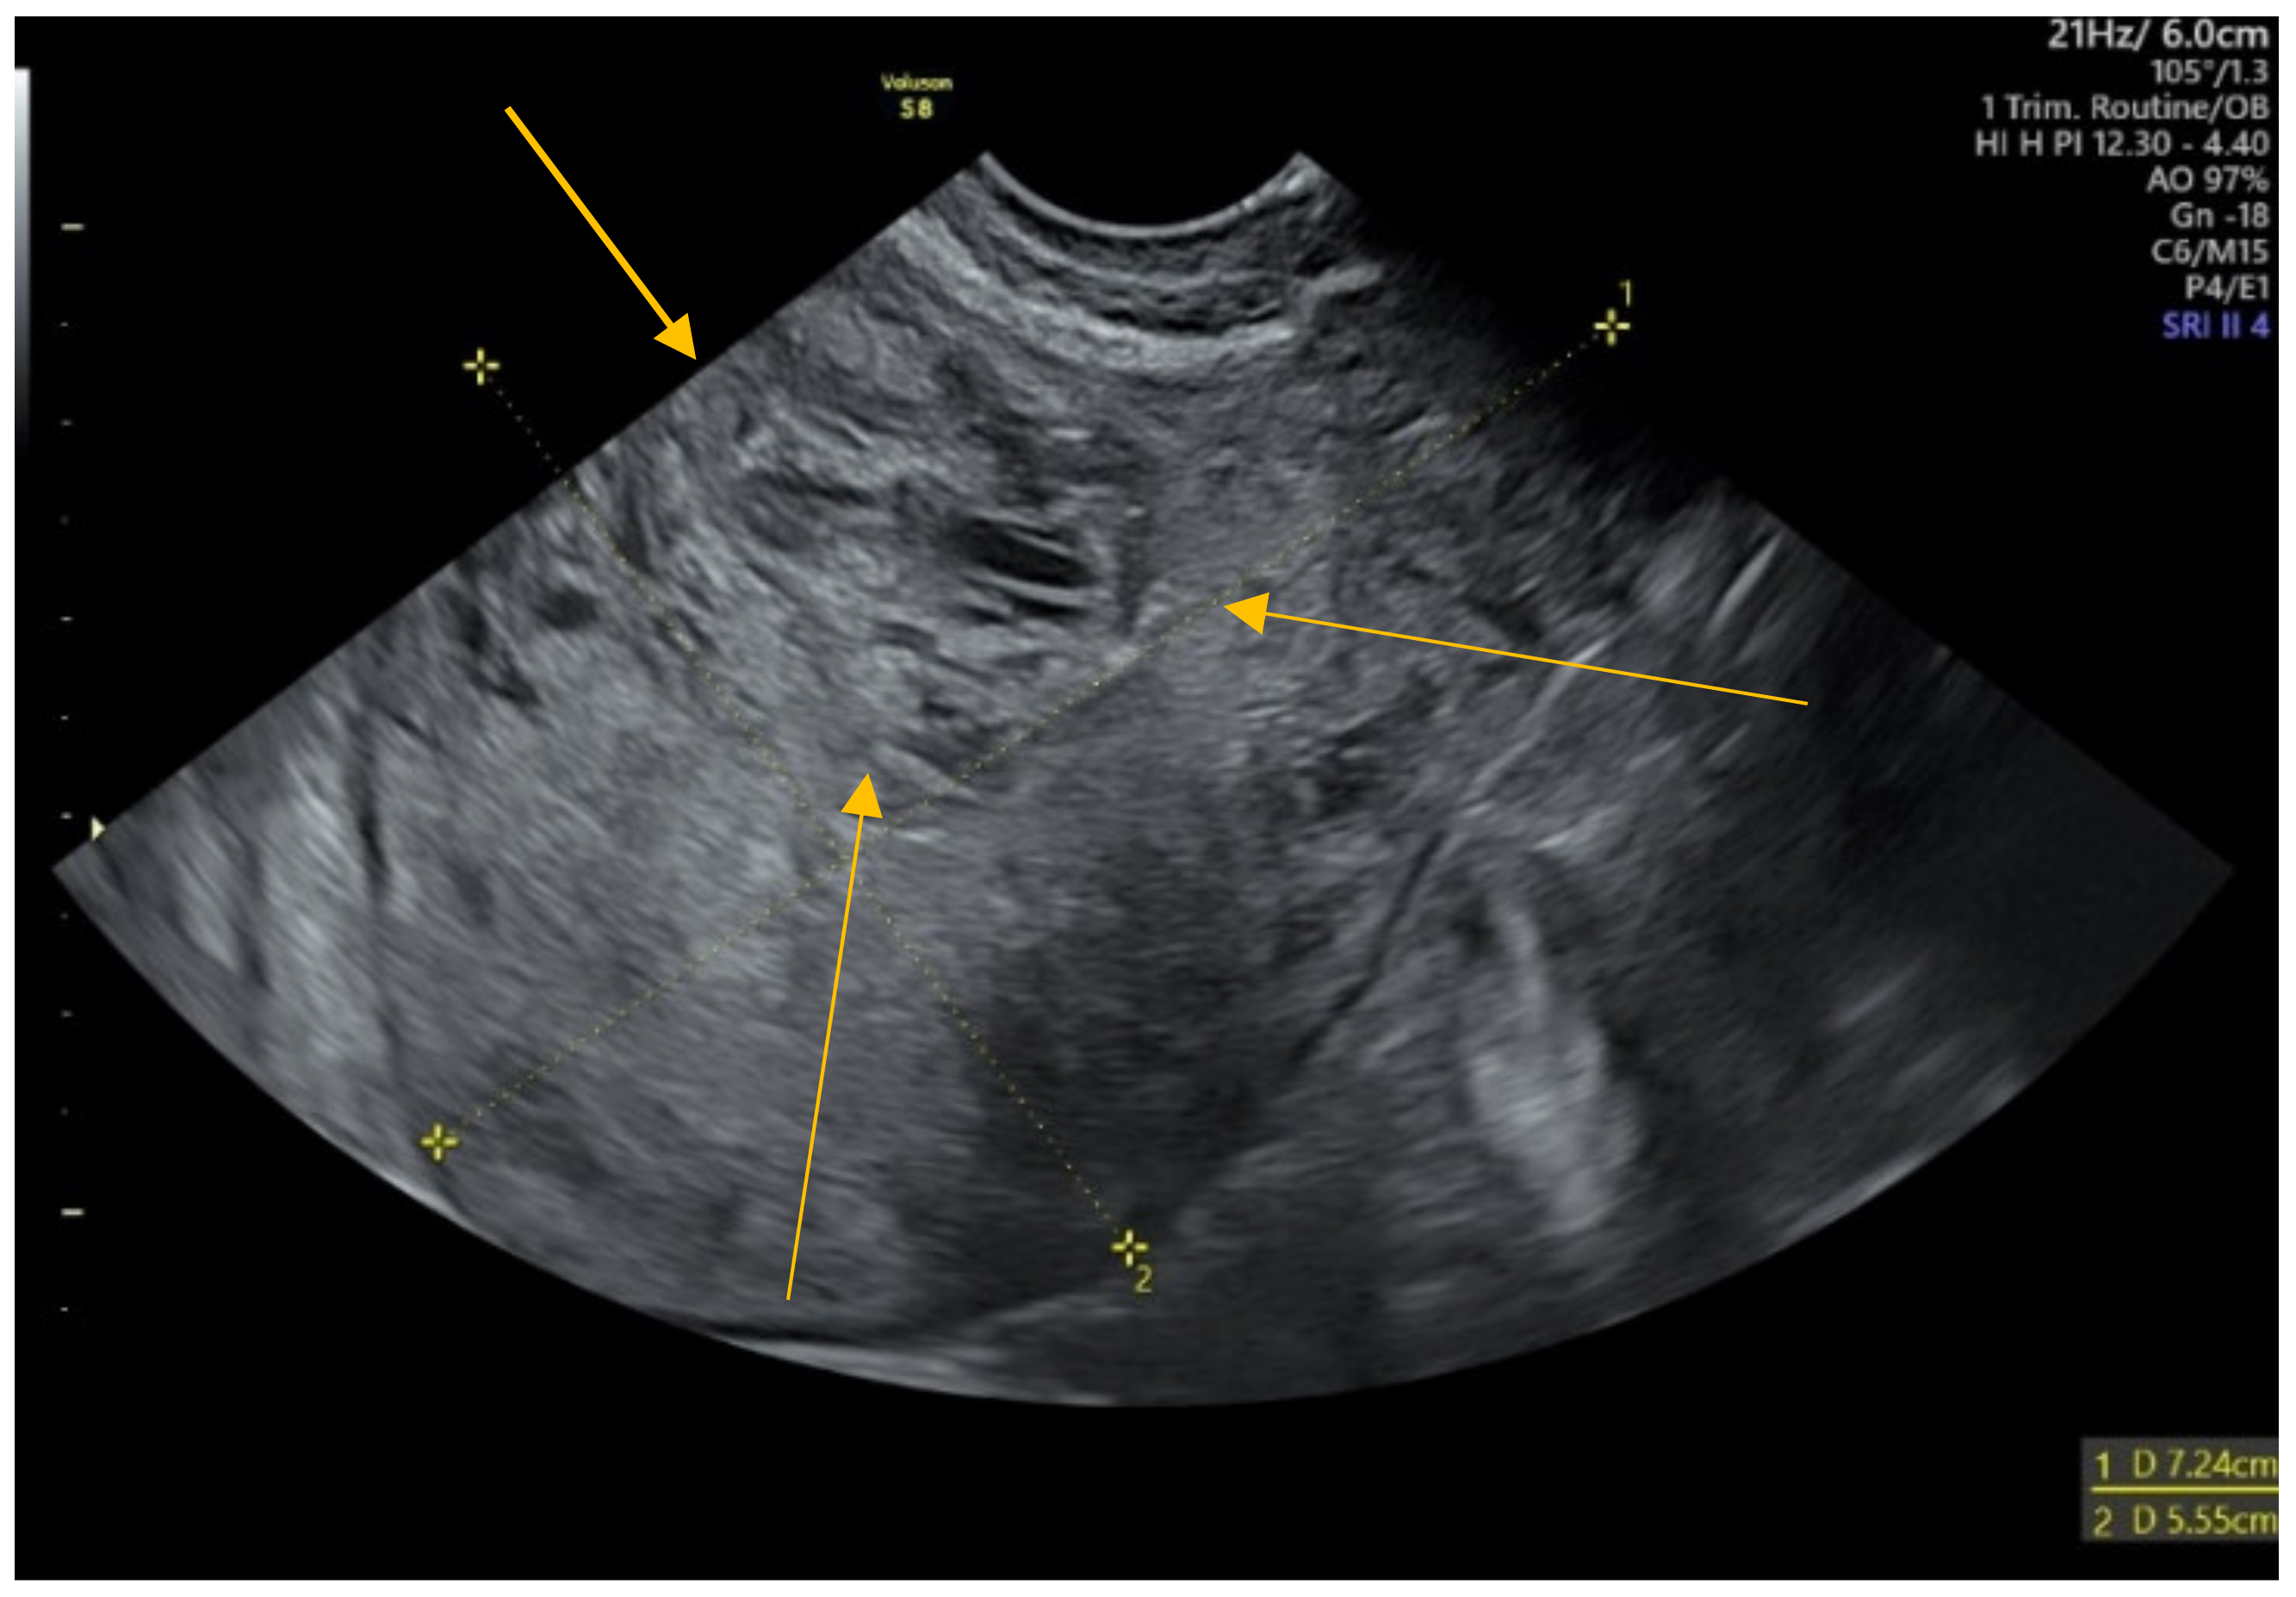

2. Case Presentation